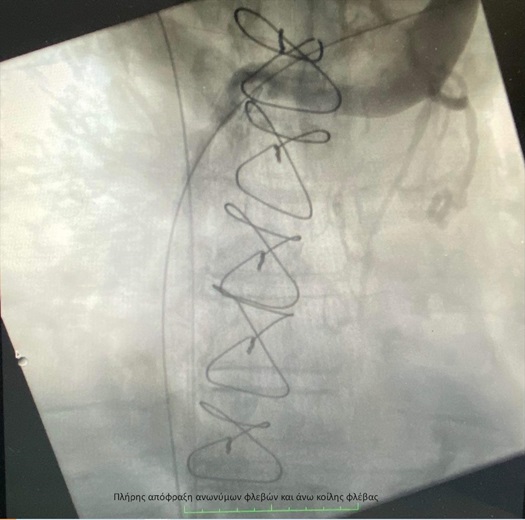

Ασθενής 66 ετών με ιστορικό νεοπλασίας προσήλθε στο ΙΑΣΩ Θεσσαλίας με έντονο πόνο και οίδημα στα δύο άνω άκρα, τον τράχηλο και την κεφαλή. Παρελήφθη άμεσα από την Α΄ Αγγειοχειρουργική Κλινική και του διενεργήθηκε αξονική φλεβογραφία, η οποία έδειξε πλήρη απόφραξη της δεξιάς ανώνυμης φλέβας, νηματοειδή ροή στην αριστερή ανώνυμη φλέβα - λόγω πιεστικών φαινομένων από νεοπλασματικό ιστό - καθώς και εκτεταμένο παράπλευρο δίκτυο στον ανώτερο θώρακα (σύνδρομο άνω κοίλης φλέβας). Εξαιτίας της προχωρημένης κλινικής εικόνας τέθηκε η ένδειξη για ενδοαυλική αποκατάσταση.

Η ομάδα της Α´ Αγγειοχειρουργικής κλινικής υπό την καθοδήγηση του Διευθυντή Αγγειοχειρουργού Νεκτάριου Γαλάνη και την πολύτιμη συνδρομή του Ακτινολόγου Βασίλειου Δημαρέλου και του Αναισθησιολόγου Δημήτριου Ζωσιμίδη, προχώρησε σε αγγειοπλαστική των πλέον στενωτικών σημείων των ανώνυμων φλεβών και της άνω κοίλης φλέβας υπό ακτινοσκοπική καθοδήγηση. Η προσπέλαση ήταν διπλή με παρακέντηση των μασχαλιαίων φλεβών αμφότερων των άνω άκρων και τοποθέτηση δίδυμων στεντ εύρους 12χλστ και μήκους 80χλστ στη δεξιά και αριστερή ανώνυμη φλέβα και την άνω κοίλη φλέβα, που αποκατέστησαν τη βατότητα των ανωτέρω αγγείων .